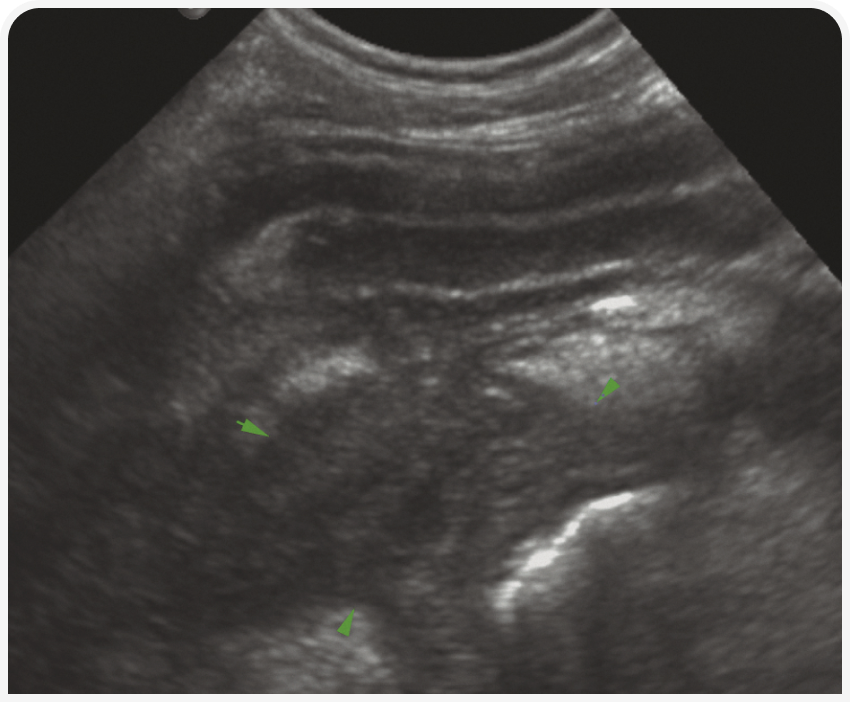

Паренхима печени однородная, слегка зернистой эхотекстуры, гипоэхогенна относительно серповидной жировой подушки и селезенки (Рисунок 3) и изо- или гипоэхогенна относительно правой почки (1). Контуры печени должны быть гладкими и ровными, очерченными тонкой гиперэхогенной капсулой. Разделение долей печени должно быть четким, если только в брюшной полости нет свободной жидкости. Печеночные вены легко визуализируются в паренхиме печени в виде трубчатых анэхогенных структур, а ветви воротной вены отличаются от системных вен гиперэхогенными стенками. Кроме того, по степени видимости портальных сосудов можно оценивать эхогенность ткани печени.

Как и на рентгенограмме, размер печени оценивают субъективно – по каудовентральному краю, который не должен выходить за пределы дна желудка. Правые доли проецируются более дорсально, часто лучше оценивать их в каудальном межреберном окне в 10-м или 11-м правом межреберье. В этом окне также удобно оценивать желчный пузырь, который обычно содержит анэхогенную жидкость и имеет очень тонкую гиперэхогенную стенку. У большинства собак среднего возраста в желчном пузыре выявляется подвижный эхо-материал. У кошек такое содержимое встречается довольно редко и требует дополнительного исследования функции желчевыводящих путей. Внутрипеченочные желчные протоки в норме не видны.

В основном при ультразвуковом исследовании можно выявить изменение размеров (чаще всего гепатомегалию) и эхогенности печени или наличие в ней узелка или объемного новообразования. Ультразвуковое исследование позволяет с высокой чувствительностью обнаруживать изменения паренхимы, но оно неспецифично, поэтому любые изменения следует интерпретировать с учетом клинических проявлений. Например, гиперэхогенную гепатомегалию на фоне желтухи у кошек можно с высокой вероятностью считать проявлением липидоза, а у собак с диабетом считать вариантом нормы. При этих двух заболеваниях паренхима печени также будет разрежена (Рисунок 4). Острый гепатит может характеризоваться гипоэхогенной гепатомегалией, а хронический – гетерогенностью тени и неровными краями печени.